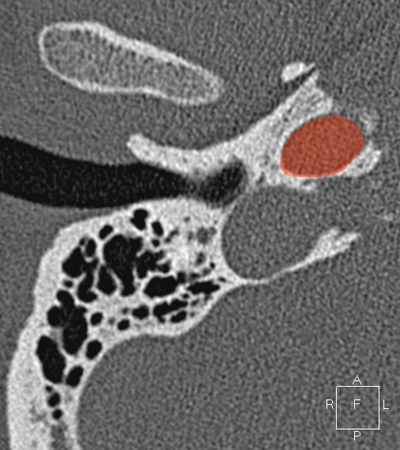

Sigmoid sinus Jugula bulb Horizontal petrous carotid Groove for tympanic (Jacobson's) nerve Facial nerve (f3), mastoid segment Anterious wall of bony EAC (tympanic bone) Mandibular condyle

Radioanatomy of Temporal bone